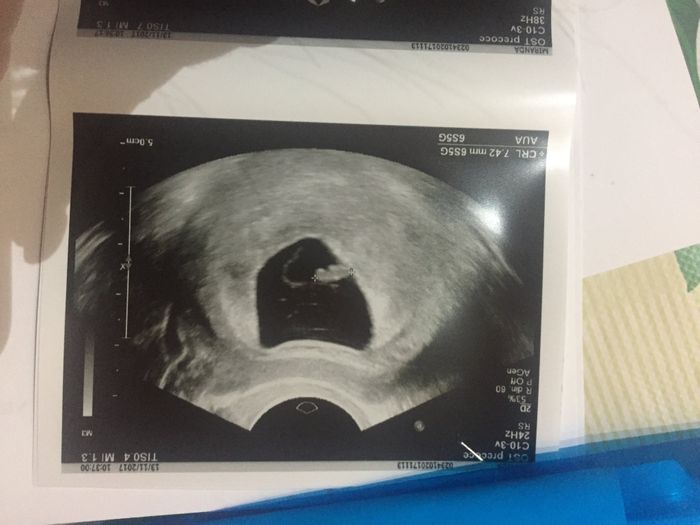

Ho caricato una foto nel post di Ilaria

Buonasera ragazze.. oggi sn andata a fare la prima eco e sn di 10 settimane purtroppo mi hanno detto che l embrione è troppo piccolo quindi nn sn riusciti a sentire il battito.. ora ho l altra eco lunedi ma se nn è cresciuto e nn si sente il battito...